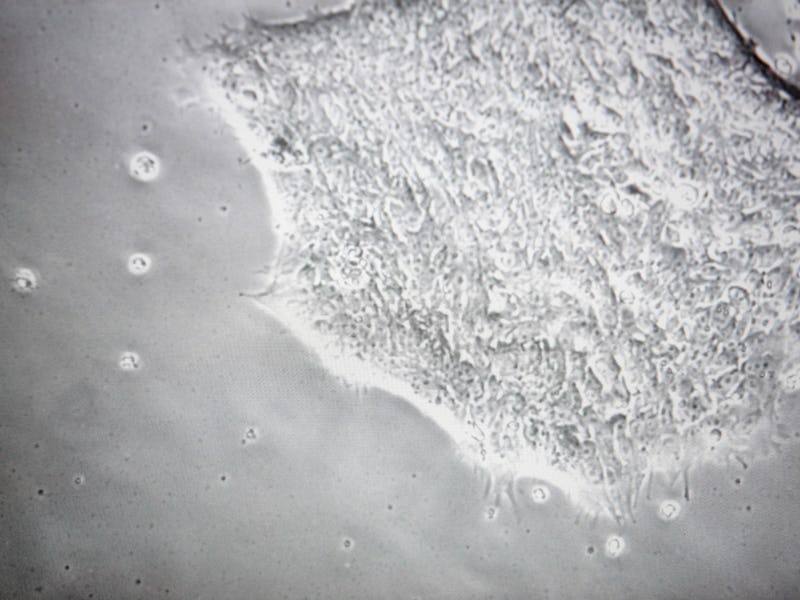

It’s been five months since a Chinese group from Sun Yat-Sen University announced they’d created the world’s first genetically modified human embryo, and while arguments are still raging over the ethics of that leap, the Hinxton Group, with its membership of stem cell researchers, bioethicists, and policy experts, is now saying it was of “tremendous value” to science.

The health benefits of such work are not simply speculative. In the case of the Chinese embryo, researchers altered the mutant DNA responsible for beta thalassemia, a life-threatening blood disorder affecting about 100,000 people. On the other side of the debate are reasonable concerns about the ethics of making a “designer baby” and the fact that the Chinese breakthrough only came after editing failed in unpredictable ways in multiple embryos along the way. Those concerns are just some of the reasons the U.S. National Institutes of Health still refuses funding for any gene-editing in human embryos.